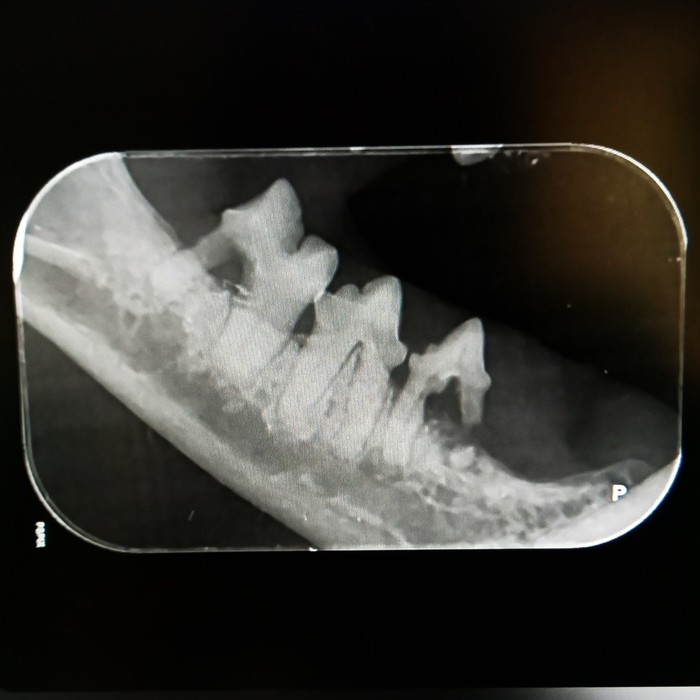

Rentgeny zubů se využívají na zobrazení hlubších vrstev zubů, kořenového systému zubů, posouzení parodontu a čelistních kostní.

Při rentgenologickém vyšetření posuzujeme následující struktury:

Korunka zubu: přítomnost a celistvost skloviny, šířka dentinu a jeho případné patologie, šířka dřeňové dutiny, celistvost zubu, při frakturách rozsah zlomenin, hledáme resorptivní léze, kazy, částečné/úplné fraktury, změny tvaru a celistvosti korunky

Krček zubu: celistvost krčku, resorptivní léze, kazy, fraktury

Kořen zubu: posouzení cementu na povrchu zubů, dentinu, dřeňové dutiny, fraktur kořenů, tvaru kořenů a jeho případných výběžků, přítomnosti tzv. pulpálních kamenů, osteoresorptivních lézí

Čelist: posouzení případných periapikálních reakcí, přítomnosti, úbytku či změny struktury alveolární kosti, přítomnost zlomenin čelisti či nádorového procesu, ne/přítomnost některých zubů

kořenové anomálie

kořeny mléčných zubů

periapikální absces

polámané kořeny v čelisti

vstřebávající se kořen špičáku

resorptivní léze